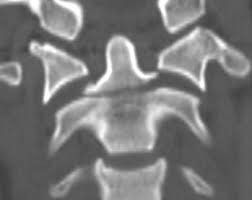

Dieser Bereich stellt den oberen Teil der Wirbelsäule dar der aus den Wirbelkörpern Bandscheiben Muskeln Bändern und den Nervenbahnen besteht. Der erste Halswirbel wird als Atlas bezeichnet der zweite als Axis. Denn der Eingriff birgt Risiken gerade für ältere Betroffene die Operationen nicht mehr so gut verkraften.

Diese Wirbelbrüche sind zwar nicht instabil und die Gefahr von Schäden am Rückenmark ist sehr gering dennoch können sie starke Schmerzen und eine Fehlstellung der Wirbelsäule verursachen. Er kann an einem der sieben Halswirbel entstehen. Bei jüngeren Betroffenen sind in der Regel Verkehrs- und Sportunfälle die Ursachen für einen Wirbelbruch bei älteren Menschen geht ein Wirbelbruch vor allem auf eine schwache Knochenstruktur durch Osteoporose zurück.

Bei Halswirbelbrüchen ist eine Zervikalstütze Halskrause notwendig. Unter einem Genickbruch versteht man allgemein einen Bruch der Halswirbelsäule.

Er kann an einem der sieben Halswirbel entstehen. Der erste Halswirbel wird als Atlas bezeichnet der zweite als Axis. Dieser Bereich stellt den oberen Teil der Wirbelsäule dar der aus den Wirbelkörpern Bandscheiben Muskeln Bändern und den Nervenbahnen besteht. Denn der Eingriff birgt Risiken gerade für ältere Betroffene die Operationen nicht mehr so gut verkraften. Er kann an einem der sieben Halswirbel entstehen. Die Schmerzen können einen älteren Menschen ans Bett fesseln und seiner Mobilität berauben und hier lauert die eigentliche Gefahr. Nur 15 bis 20 Prozent aller Wirbelsäulenverletzungen betreffen die Halswirbelsäule. Unter einem Genickbruch versteht man allgemein einen Bruch der Halswirbelsäule. Diese Wirbelbrüche sind zwar nicht instabil und die Gefahr von Schäden am Rückenmark ist sehr gering dennoch können sie starke Schmerzen und eine Fehlstellung der Wirbelsäule verursachen.

Beschreibung Ein Genickbruch bezeichnet einen Wirbelbruch der Halswirbelsäule. Bei einem jungen Sportler ist man eher geneigt eine Operation durchzuführen als bei einem alten bettlägrigen Patienten den man so ohne großen Nutzen für die Dauer von weiteren 2 Monaten in ein. Bei einem Wirbelbruch durch Osteoporose raten viele Ärzte zu einer Operation. Nur 15 bis 20 Prozent aller Wirbelsäulenverletzungen betreffen die Halswirbelsäule. Bei instabilen Brüchen besteht dagegen die Gefahr dass Teile des Bruches die Nervenwurzel im Spinalkanal einengen und dadurch neurologische Ausfälle wie Lähmungen folgen. Weil der Wirbelsäulenkanal der Halswirbelsäule sehr eng ist wird bei der Verletzung in 70 Prozent der Fälle zusätzlich auch das Rückenmark geschädigt. Der erste Halswirbel wird als Atlas bezeichnet der zweite als Axis.